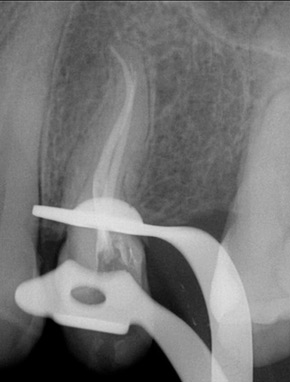

Tratamiento que se realiza con la finalidad de salvar un diente. De no ser tratado tendría que ser extraído; necesario cuando un trauma o caries daña al tejido interno del diente (pulpa).

El tratamiento consiste en la eliminación del tejido pulpar dañado, así como la desinfección y el sellado para poder recibir una prótesis y evitar futuras infecciones.